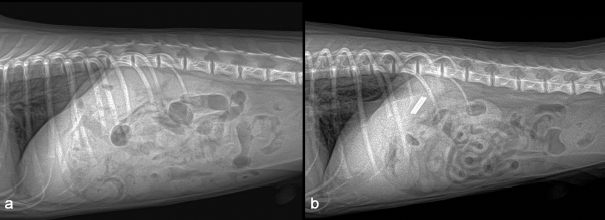

A 1-year-old neutered male Maltese dog weighing 1.4 kg was referred to the Veterinary Teaching Hospital showing microhepatica (Fig. 1a) and hyperammonemia. The dog did not show clinical signs related to portosystemic shunt previously. Although its postprandial ammonia level was in the reference range [18 μmol/l, reference interval (RI): 0–98 μmol/l], hypoalbuminemia (2.1 g/dl, RI: 2.6–3.3 g/dl) and increased levels of serum bile acid (177 μmol/l, RI: 0–25 μmol/l), alanine transaminase (ALT) (254 IU/l, RI: 21–102 IU/l), and alkaline phosphatase (ALP) (1347 IU/l, RI: 29–97 IU/l) were identified. No abnormalities, including cardiac murmur, were observed during physical examination. For a more thorough examination, computed tomography was used, and a CPSS (porto-caval shunt) was diagnosed (Fig. 2a and b). After preoperative medical stabilization, surgery was performed for shunt attenuation. Anesthesia was induced with propofol (8 mg/kg, IV) and maintained by isoflurane. Perioperative pain was managed by tramadol (5 mg/kg, IV). From the xiphoid process to the pubis, a standard ventral midline approach was taken. After dissecting the shunt from surrounding tissues, portal pressure was measured from the jejunal vein. Baseline portal pressure was measured to be approximately 7–8 mmHg (RI: 6–10 mmHg). It increased to 13–14 mmHg after temporary complete occlusion of the shunt. The shunt was attenuated using a cellophane band. The abdominal cavity was closed in a routine manner. Its recovery from anesthesia was uneventful. Postprandial serum bile acid (12 μmol/l), albumin (2.6 g/dl), and ALT (29 IU/l) levels returned to their normal ranges at 1 month after the operation. Its serum ALP level also decreased to 430 IU/l, although it was above the RI. An increase in liver size was observed by abdominal radiographs 1 month after surgery (Fig. 1b). Because the majority of the CPSS anomalies were cured throughout the follow-up period, the dog was able to return to normal life without the need for supporting medicine. One year after surgery, the dog was presented to the Veterinary Teaching Hospital for exercise intolerance. Blood gas analysis revealed hypoxemia (73.6%, RI: 95%–99%). A cardiac murmur was auscultated. When compared with thoracic radiographs evaluated at the time of the operation (Fig. 3a and b), the vertebral heart scale increased from 10 to 11.7, indicating generalized cardiomegaly (Fig. 3c and d). Following echocardiography revealed ASD and pulmonary hypertension (Fig. 4a and b). A bubble study confirmed right-to-left shunt. Surgical or interventional therapy was not contemplated due to the dog's tiny size (1.7 kg) and reversed interatrial shunt. Thus, medical treatment was performed to reduce pulmonary hypertension (sildenafil, 1.5 mg/kg, PO, q12 hours). Hypoxemia was improved (94%) after a month of treatment. The dog's activity intolerance had been overcome, according to the owner. As a response to the medical treatment was generally good, therapy was still maintained without changing medication for the next 16 months after diagnosis of the ASD.

Fig. 4. Echocardiography (right parasternal long-axis four-chamber view) showed an atrial septal defect (a) and color Doppler revealed a right-to-left shunt (b).

The present study described a dog with two types of vascular anomalies. Similar to a previous study (Greenhalgh et al., 2010), the dog showed a good prognosis after surgical attenuation of the CPSS. Cardiomegaly was not seen on preoperative thoracic radiographs, despite the fact that ASD was suspected at the time of CPSS diagnosis. ASD is generally a well-compensated disease (Chetboul et al., 2006) and the dog may show no clinical symptoms over 2 years. When it was presented 1 year after the operation, the chief complaint was exercise intolerance of the dog. Compared with the previous clinical data on the dog, it could be suspected that ASD caused pulmonary hypertension, which might have resulted in a right-to-left shunt (Guglielmini et al., 2002). This hemodynamic physiology is generally defined as Eisenmenger’s syndrome, which can cause cyanosis and exercise intolerance (Berger et al., 2010). In veterinary medicine, surgical treatment for ASD is challenging for small-sized dogs (Pelosi et al., 2013). Although a case of ASD closure in a toy poodle was recently published (Sugimoto et al., 2020), owing to the dog's pulmonary hypertension and reversed interatrial shunt, surgical and interventional therapy for the dog was not explored in the current investigation. Surgical treatment for Eisenmenger’s syndrome, such as heart-lung transplantation, has been performed in human medicine. However, its morbidity and mortality remain high (Waddell et al., 2002). As an alternative to surgical treatment, medical management by sildenafil can be effectively applied to patients with this condition (Garg et al., 2011). The dog in the present study also responded well to sildenafil, and its clinical symptoms were resolved. In previous human medicine studies, about 9% to 30% of patients have CPSS concurrent with ASD (Franchi-Abella et al., 2010; Kim et al., 2012). Like human medicine, this study reports a rare case of CPSS concurrent with ASD in a dog. Because congenital heart illnesses are easily recognized by echocardiography, it is also suggested for dogs with CPSS to get an echocardiogram for early detection of additional cardiovascular defects, even if there are no symptoms.